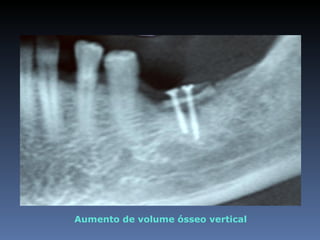

Ademir Lopes

Idade – 66 anos

Sexo – Masculino

Raça – Caucasiana

ASA – II

Data- 24-04-2012

Diagnóstico: Desdentado parcial

bi-maxilar

Plano de tratamento: Reabilitação das áreas

desdentadas 1.5, 1.6, 4.6 reabilitadas com aloenxertos

ósseos frescos-congelados, para posterior reabilitação

pretética.

Área previamente enxertada

Aumento de volume ósseo vertical